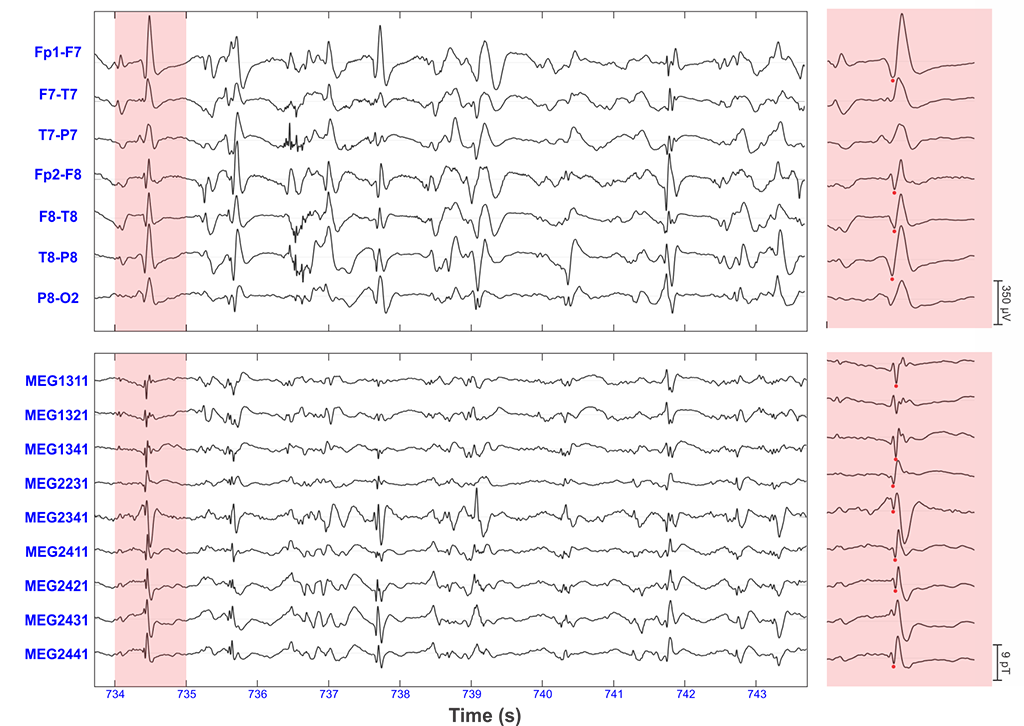

Epilepsy-Figure-2

Figure 2: Epileptic spikes detected with HD-EEG and MEG. Portion of simultaneously recorded scalp HD-EEG and MEG signals with frequent spikes. The highlighted section is one second that contains one sharp wave shown on the right panels in an extended time scale display. Red dots indicate the peak of the spike. Figure adopted by Papadelis et al. (2016).